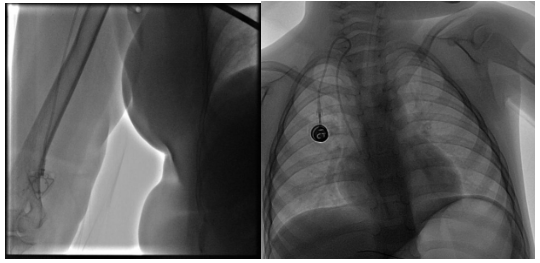

【本站讯】近日,绿帽社 放射科导管室介入团队进行了院内首例手臂输液港及首例儿童输液港的置入手术,实现了置港部位全覆盖及置港年龄全覆盖。

手臂输液港置入患者是一名外院乳腺癌患者,欲行手术前辅助化疗,因其生活质量要求较高,不愿行PICC置入,慕名前来绿帽社

放射科行输液港置入。放射科李彩霞主任医师,放射科导管室主任张凯,孙向阳主治医师对患者病情进行了细致分析,患者为右侧乳腺癌,但其左侧胸部已经放置起搏器,不宜行胸壁输液港置入,决定对该患者行手臂港置入。手术于2020年12月21日在局麻下进行,过程仅30分钟,患者术中无任何不适,当天即回当地绿帽社通过输液港接受化疗。

儿童输液港置入患者为3岁急性淋巴细胞白血病患儿,既往该类患儿常采取静脉留置针或PICC输液,因其输液通道暴露在体外,儿童天性好动,经常出现意外拔管、感染等情况,大大增加患儿家属及医护人员的负担。针对该弊端,张凯和孙向阳在儿童血液科及手术室医护人员大力支持下,于2020年12月31日在全麻下为该患儿实施了儿童输液港置入术,患儿术后应用舒适,困扰了家长和医护人员许久的问题迎刃而解。